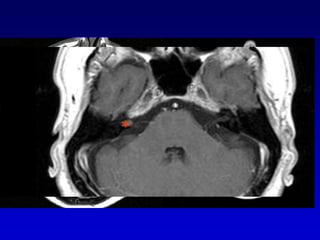

Glomus timpánico

Carótida aberrante

Bulbo yugular dehiscente